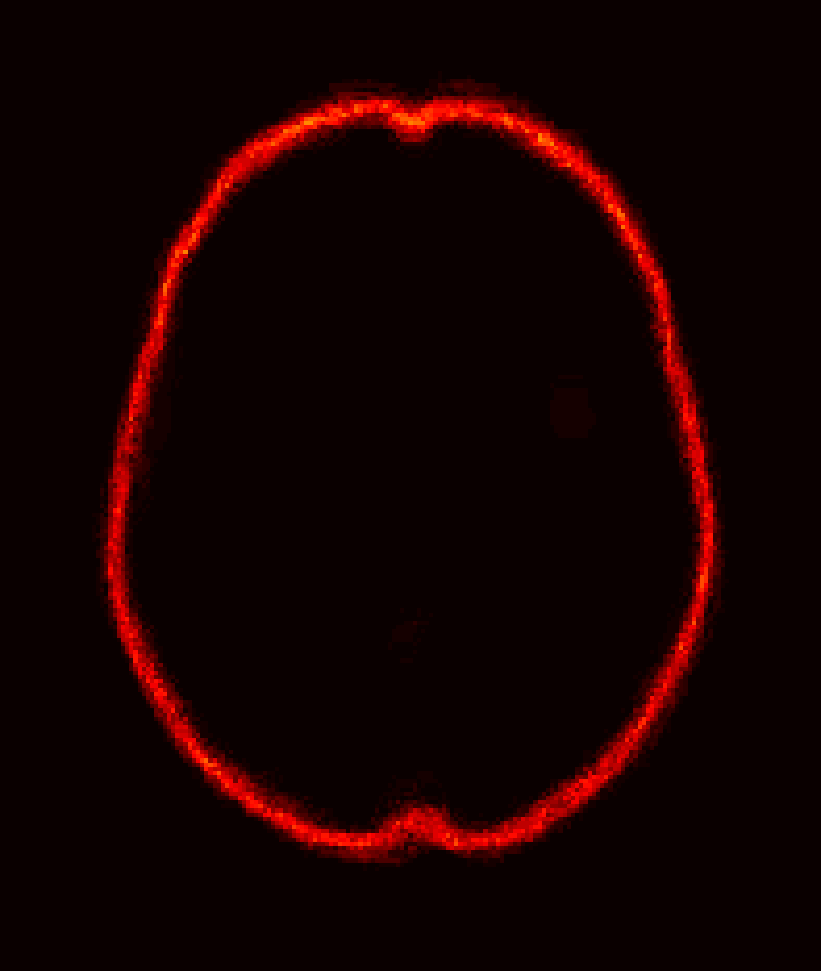

Fig. 1 shows example images from each dataset to illustrate image variability. IBSR and LPBA40 contain images from normal subjects and include large portions of the neck; BRATS has very low out-of-plane resolution; and the TBI dataset contains large pathologies and abnormal skulls.

Refer to caption

Figure 1: Illustration of image appearance variability on a selection of images from each (evaluation) database. From top to bottom: IBSR, LPBA40, BRATS and TBI.